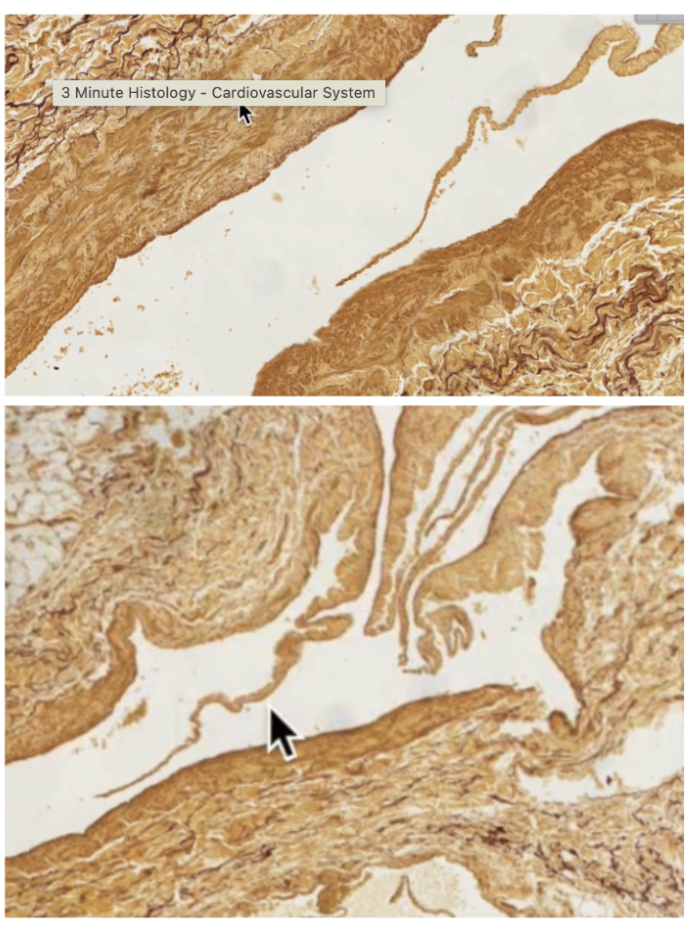

Elastic artery

Vasa Vasorum (large elastic arteries) :

Tiny branches of the artery/BV that provide nutrients to elastic arteries

Also visible as small BV in tunica adventitia

Pointer at Vaso Vasorum in tunica media left, and tunica adventitia right

Aorta, elastic artery

3 Layers:

Tunica intima (inner layer) SS endo lining

Tunica Media (eosinophilic)

Elastic lamellae (diffusion can work through them)

Nuclei in between lamellae (modified smooth muscle cells, secrete ECM)

Tunica adventitia (mostly CT)

IEL = internal elastic lamellae

mucsular artery

WAVY TUNICA INTIMA

Less elastic lamellae more smooth muscle cells

Muscular Arteries:

Thick walls, tunica media are concentrated in smooth muscle

Tunica intima has internal elastic membrane (elastic fibers), separating from tunica media

External elastic membrane separating tunica media from tunica adventitia, more diffused than internal elastic membrane

Muscular artery:

Well developed internal elastic lamellae, causing waviness of tunica intima

Muscular artery

Darker brown = internal elastic lamellae

muscular artery on left, Vein on right

muscular artery and medium vein